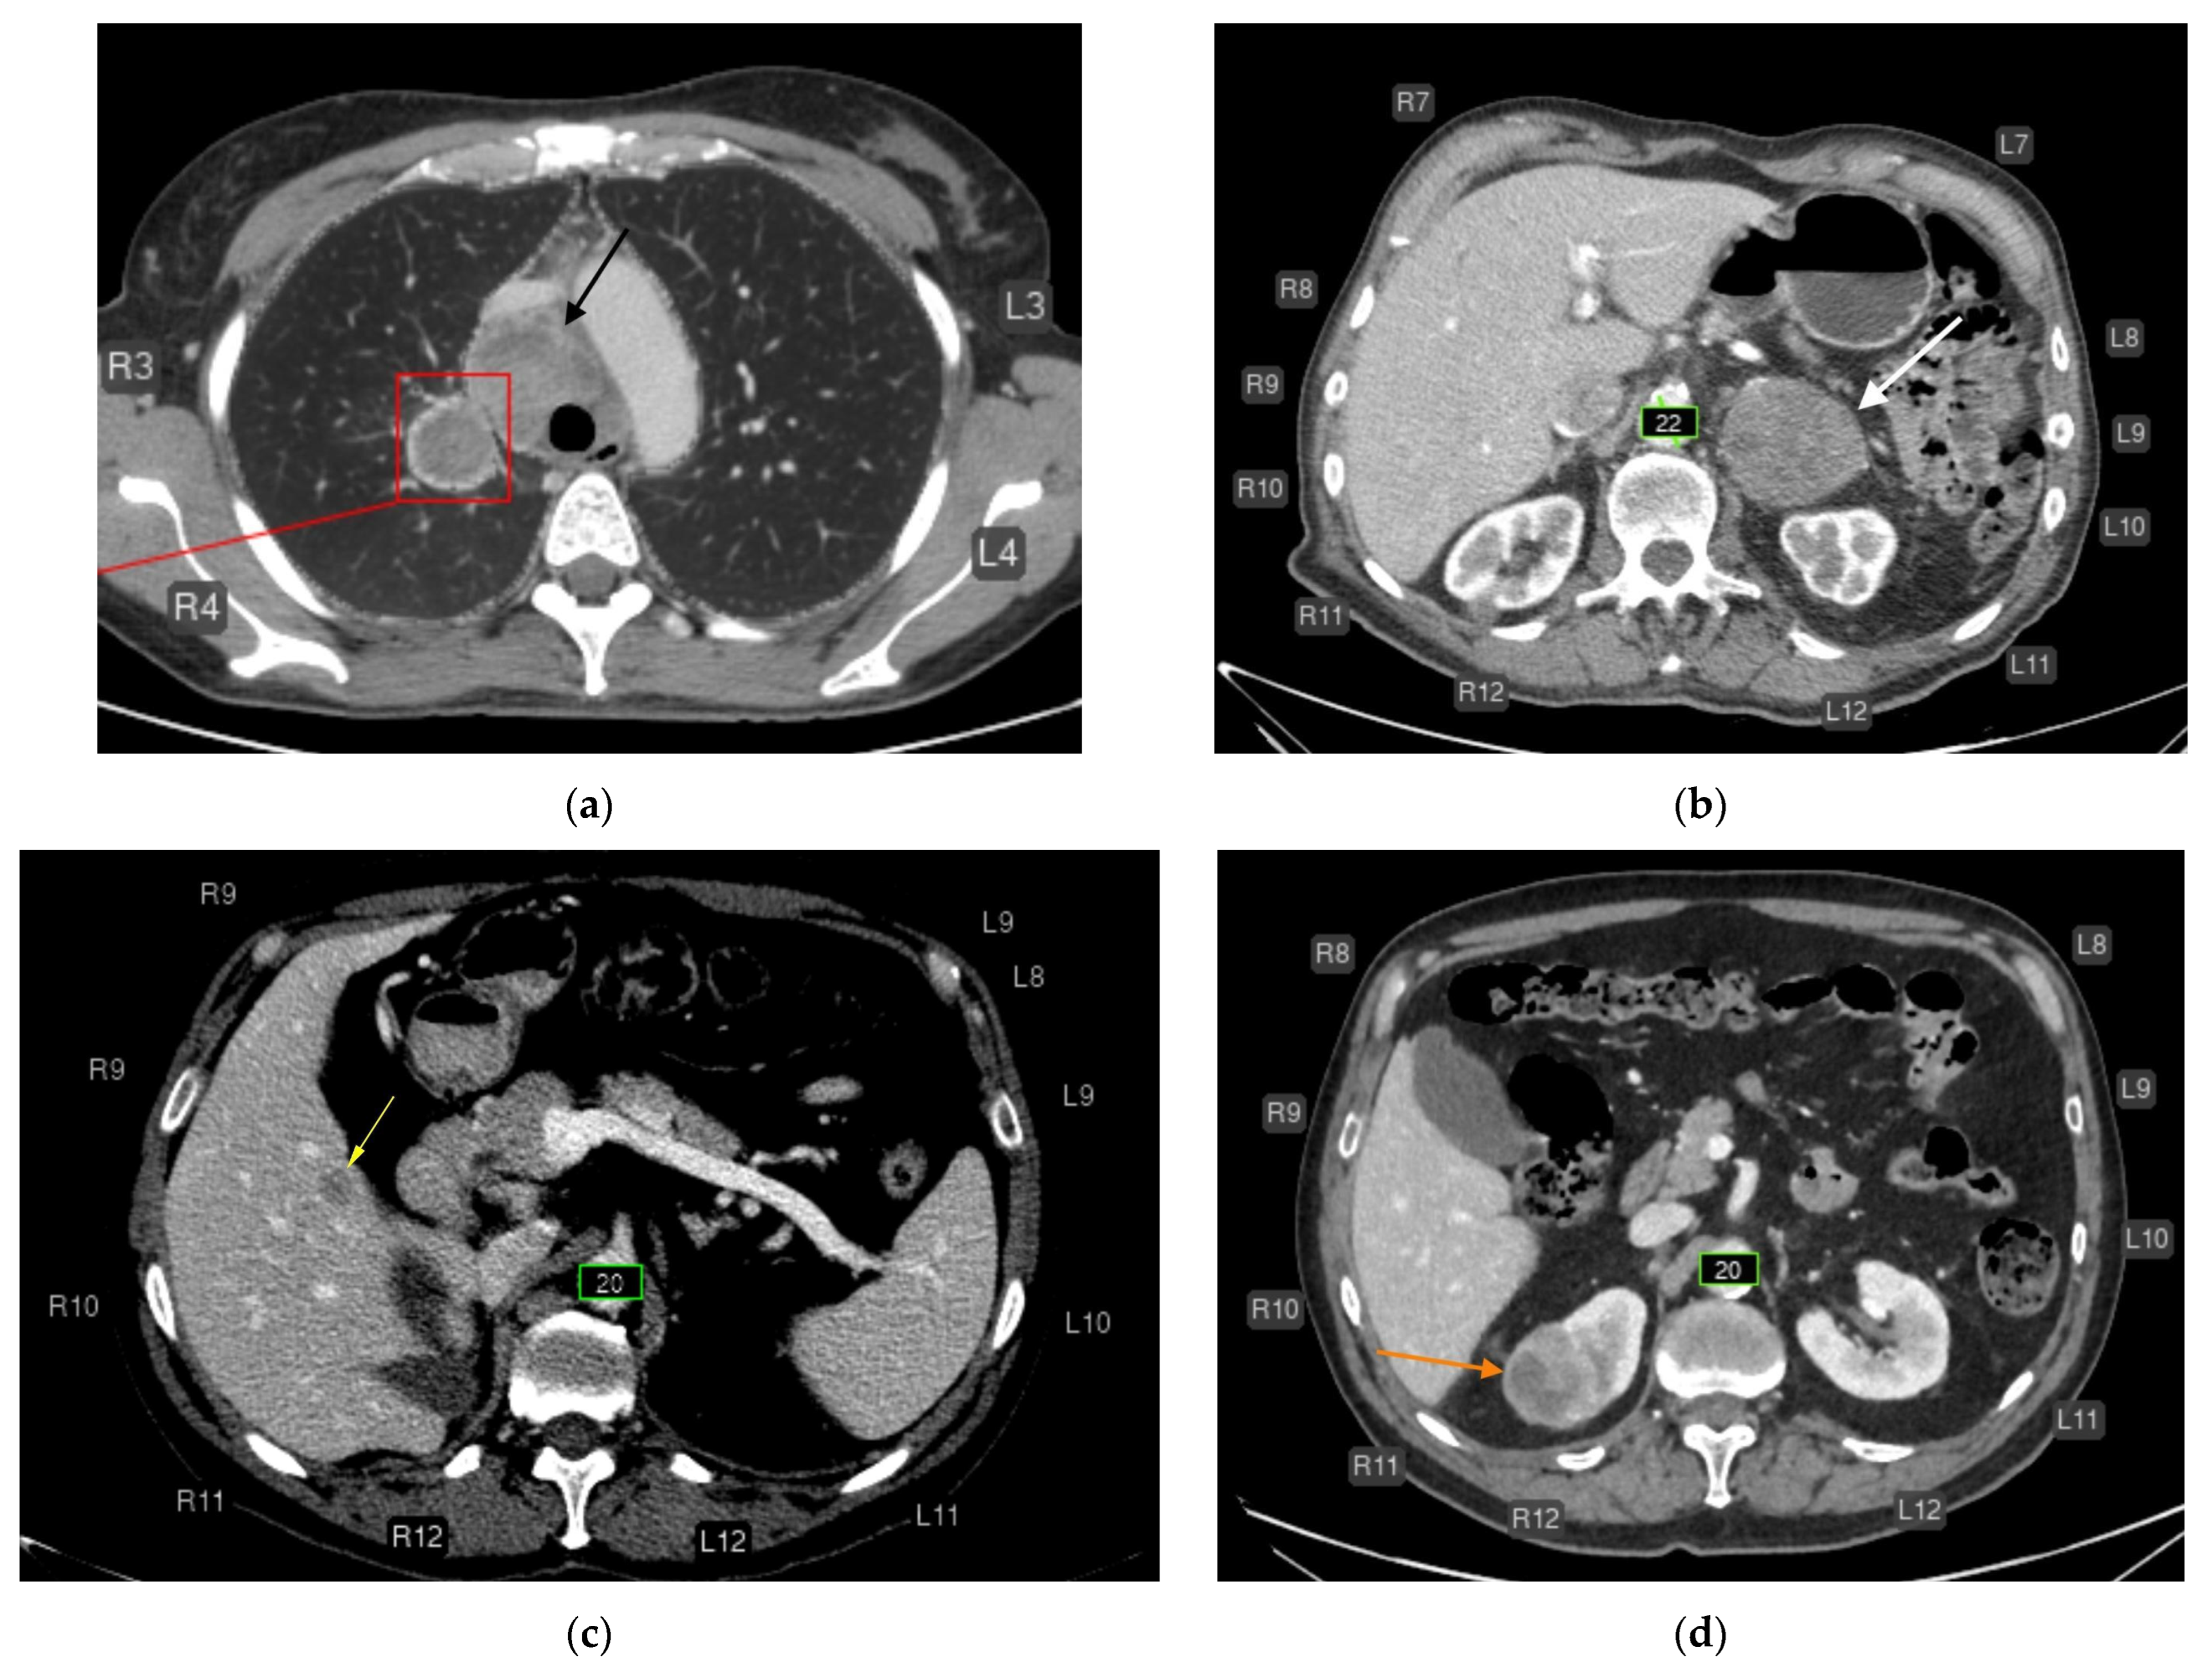

- Liver lesions (8);

- Renal lesions (2);

- Adrenal lesions (2);

- Impaired lung aeration (atelectasis, 2);

- Enlarged intrathoracic lymph nodes (3);

- Pulmonary nodule (1);

- Low vertebral body density (1);

- Urolithiasis (1) (Figure 4).